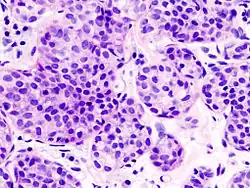

Type Prevalence Description Image

Classical 40% Round or ovoid cells with little cytoplasm in a single-file infiltrating pattern, sometimes concentrically giving a targetoid pattern

Alveolar 5% Aggregates of classical-appearing cells

Pleomorphic Classical-appearing but with pleomorphic cells. It may include signet-ring cells, or plasmacytoid cells (pictured) which have abundant cytoplasm and eccentric nuclei.